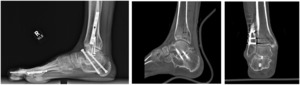

The patient underwent radiological examination (both X-Ray and CT Scan), and it was determined that the previous subtalar arthrodesis had failed (Figure 1), and the patient would require revision surgery. There was no gross evidence of infection preoperatively or intraoperatively.